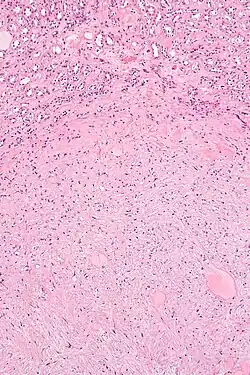

| Micrograph of a renal medullary fibroma (bottom of image). Renal tubules are seen at the top of the image. H&E stain. | |

They consist of bland spindle-shaped or stellate-shaped cells in a loose stroma. Renal tubules may be entrapped.

Low mag.

Low mag. -